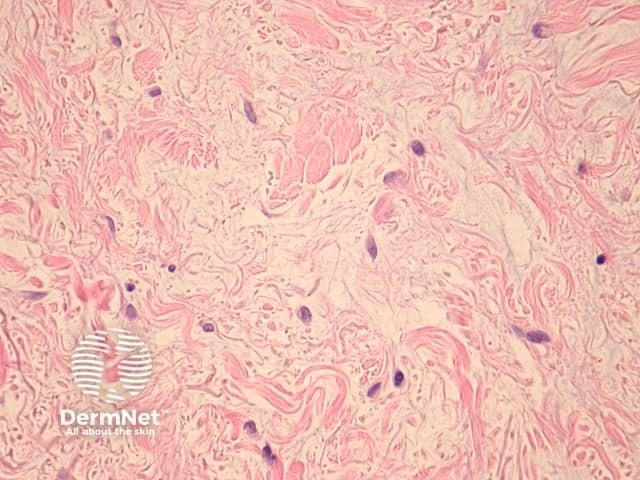

In DLE, sections reveal the dermis contains a perivascular and periadnexal lymphohistiocytic infiltrate under an interface dermatitis (figure 1). The epidermal interface activity shows degeneration of the basal layer, apoptotic keratinocytes and a marked thickening of the basement membrane (figures 2, 3). In well-established lesions, there may be marked follicular plugging (figure 4) and sometimes an epidermal reaction which may mimic a squamous cell carcinoma (verrucous lupus erythematosus). There is a characteristic lymphohistiocytic infiltrate surrounding appendages and vessels (figure 5). Deposition of dermal mucin may be impressive (figure 6).

Thickening of the basement membrane may be highlighted with periodic acid-Schiff (PAS). Mucin may be highlighted with alcian blue stain or colloidal iron.